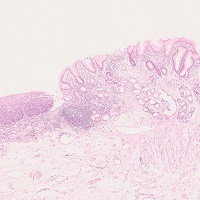

Peutz-Jeghers polyp